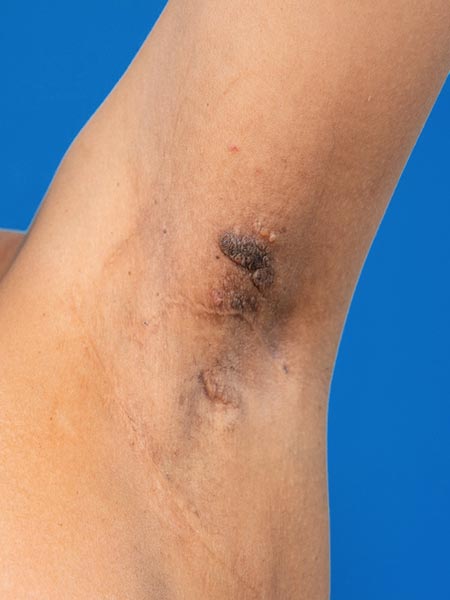

Die Patientin leidet unter einem ständigen, blutig tingierten Lymphausfluss in der linken Axilla. Aus den kleinen kutanen Lymphbläschen, die zum Teil auch exophytisch als Lymphangioma circumscriptum hervortreten, tritt pro Tag ca. 500 ml Flüssigkeit (Lymphe mit Blut) aus.

Foto der klinischen Kontrolle 3,5 Monate nach der Bleomycin-Elektrosklerotherpie. Der Befund ist viel kleiner geworden. Es findet keinerlei Flüssigkeitssekretion mehr statt, die Axilla ist trocken.